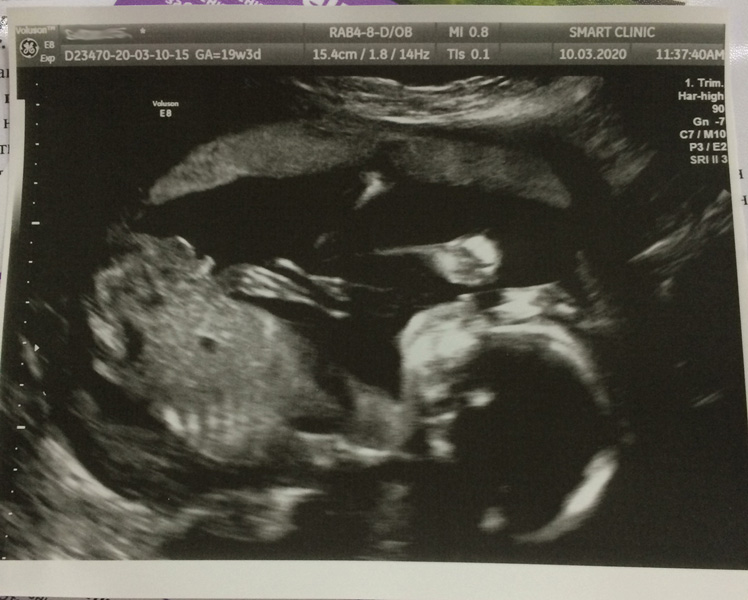

19+4: второй скрининг, фотопуз+узи ❤

2БСегодня сходила на второй скрининг, и мы ... 🥁 ... оставляем голубой кружок 😄 Не подвели меня чуйка и два хороших узиста))) Ничего парень не скрывал, лежал себе спокойно, махал руками, глотал зачем-то воды 😁

Само узи меня немного расстроило. В целом, у ребёнка всё хорошо, но обе маточные артерии больше нормы( Врач сказала, что ничего страшного, нужно наблюдать за давлением каждое утро и вечер. Ещё она заметила нарушение моего сердечного ритма, настойчиво рекомендовала сделать холтер. Срок Б по среднему получился равен сроку по О - 18+6. То есть меньше, чем по первому скринингу... И предлежание пока тазовое.

В остальном - плацента поднялась на 16 мм выше зева, длина шейки не изменилась.